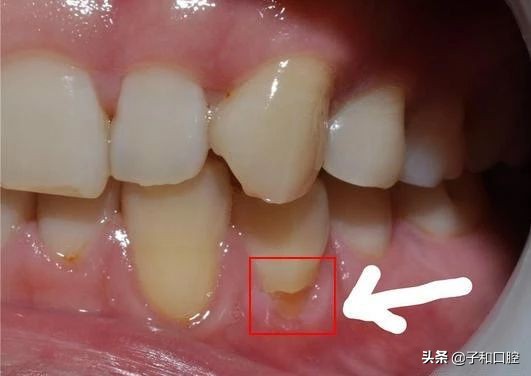

错误一:横向刷牙

据相关调查,居然有90%的人刷牙都是横着刷的,长期横向刷牙不仅破坏牙釉质,造成牙齿敏感,还容易造成牙齿楔状缺损,甚至断裂。

建议:正确刷牙应该沿着齿缝竖着刷。